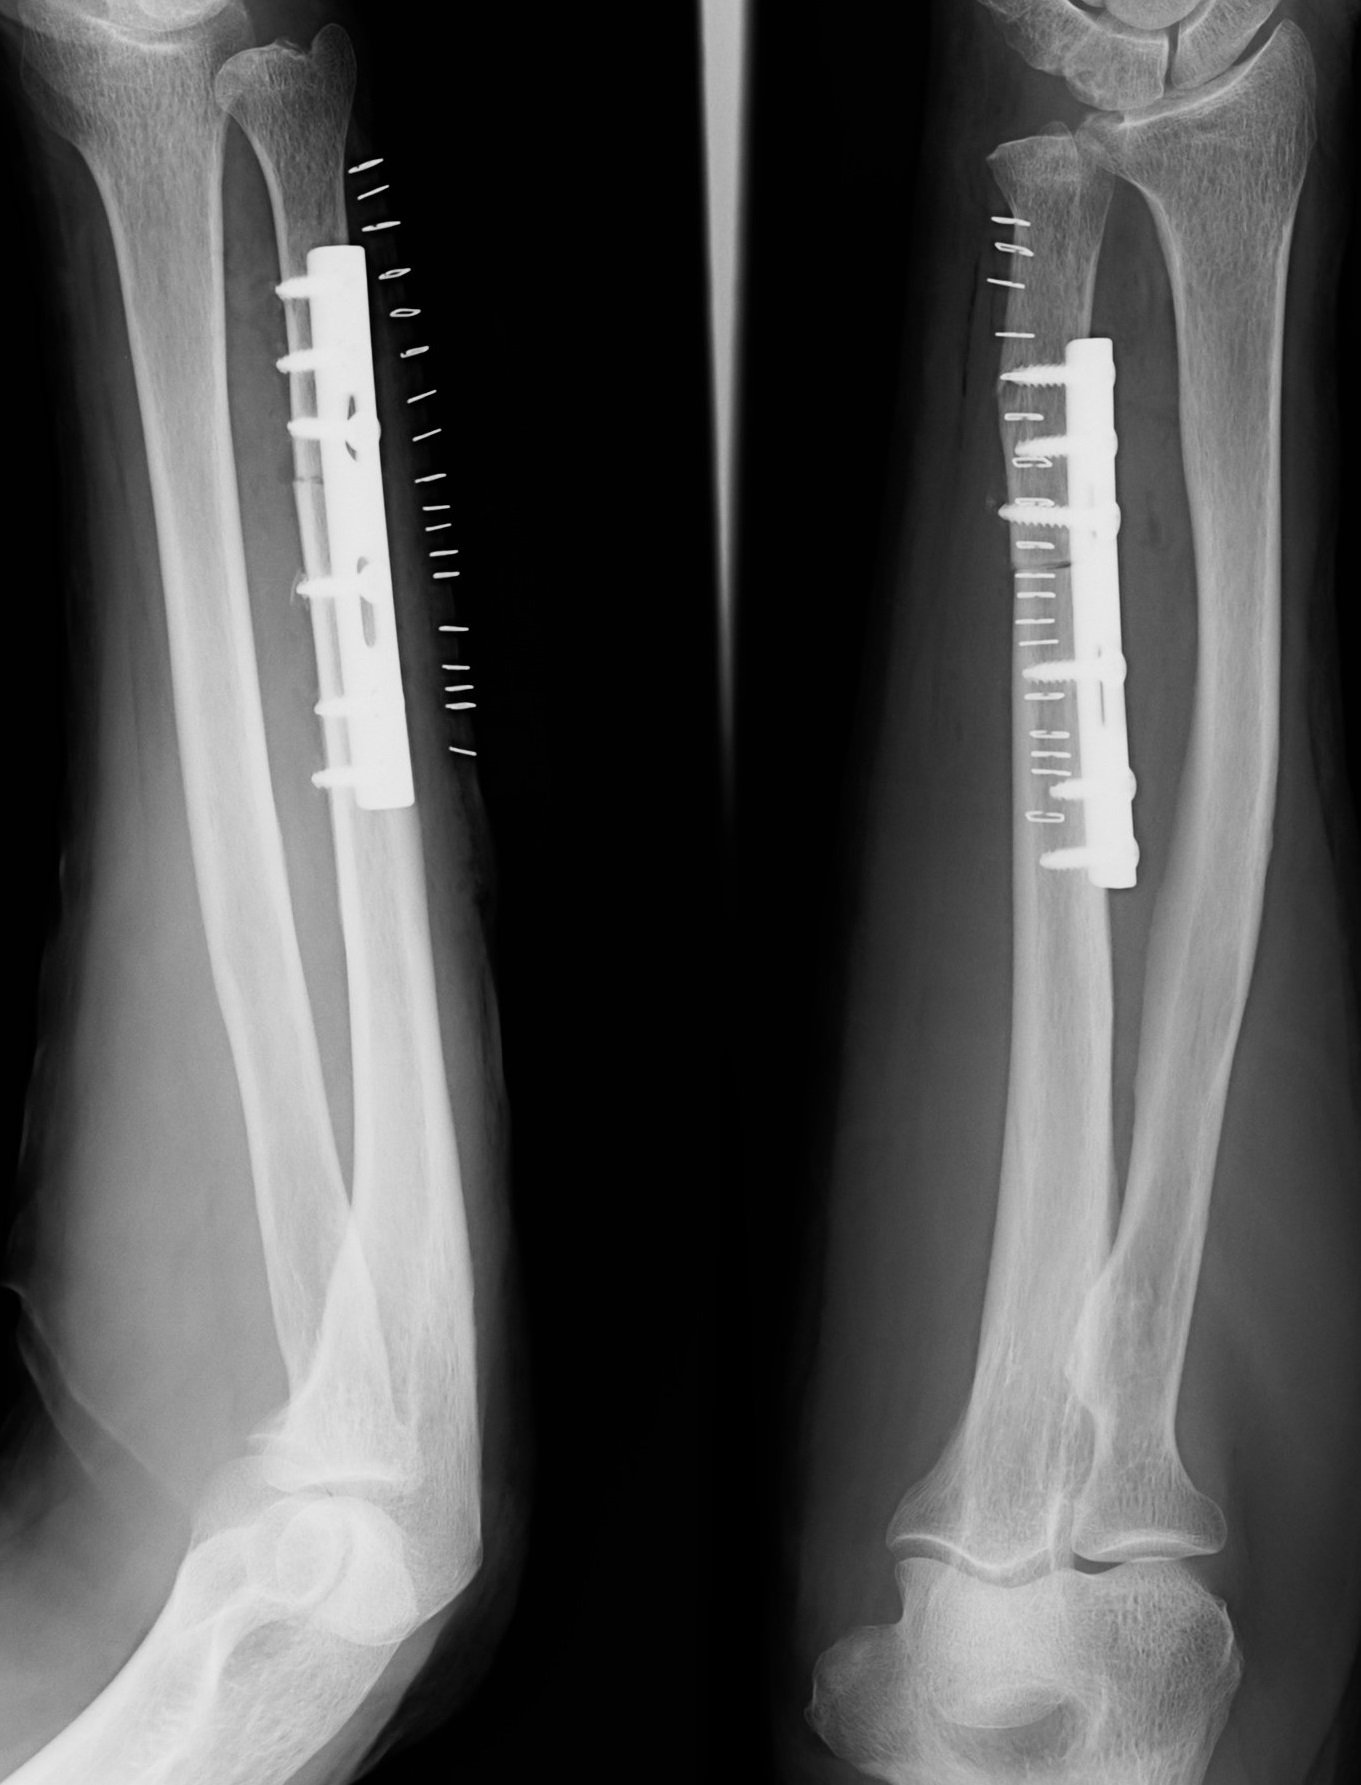

TFCC損傷尺骨突き上げ症候群druj不安定症入院手術尺骨短縮術ギプス手術跡レントゲン入院記録抜釘手術。

TFCC損傷・尺骨短縮術 入院~手術~術漁師の徒然なるブログ。